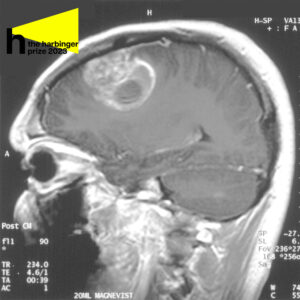

Sagittal MRI with contrast of a glioblastoma in a 15-year-old boy

Glioblastoma is notorious because of its thin branches that spread through the healthy brain tissue and makes the tumor extremely difficult to remove – a part of the tumor visible to the naked eye is only a small fraction of the entire glioblastoma. What grows underneath the healthy tissue is often the most malignant and unpredictable, because neural pathways aid the tumor in spreading to opposite sides of the brain.

While removing a tumor, surgeons often cut out healthy tissue surrounding it (called the margin) to be sure they eliminate as many damaging cells as possible. Glioblastoma often originates in the frontal and temporal lobes of the brain, critical for processing memory, emotions, auditory information, as well as sensory input. Neurosurgeons have to navigate meticulously to limit the damage to the brain.